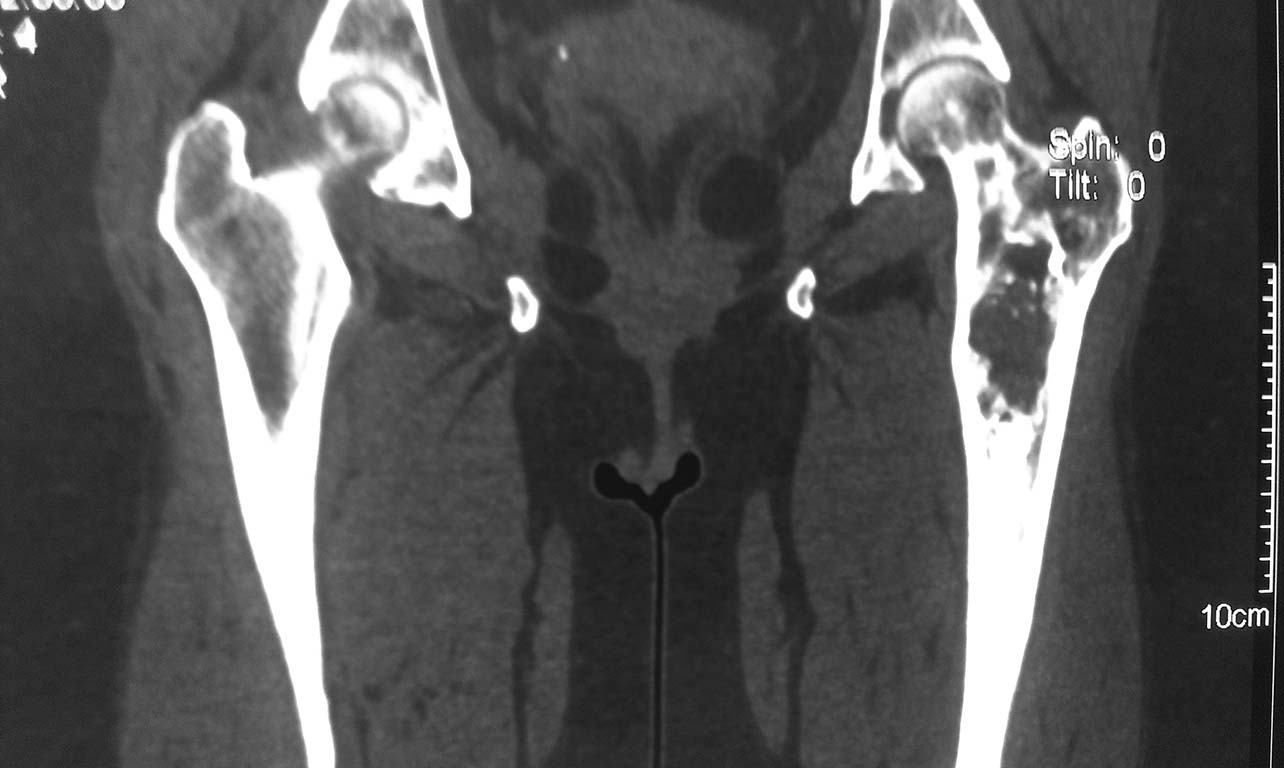

Пациентка 1952 г.р. (61 г.), поступила с жалобами на непостоянные боли в области левого тазобедренного сустава, верхней трети бедра и суставов конечностей. Anamnesis morbi: Со слов пациентки болеет в течении 2,5лет, когда появились боли в бедре и крупных суставах. Об-но: по внутренним органам без особенностей. Пальпаторно отмечается болезненность в проекции верхней – средней трети левой бедренной кости. 04.09.13г 1-м этапом произведена: Операционная биопсия из проксимального отдела левой бедренной кости. Заключение патолого - гистологического исследования: Дегенеративное поражение костной ткани с замещением незрелой фиброзной тканью. В анализах в пределах нормы. Планируем: Резекцию проксимального отдела левой бедренной кости. Тотальное цементное эндопротезирование левого тазобедренного сустава модульным имплантом. Хотелось бы услышать Ваше мнение по тактике и методам оперативного лечения.

Уважаемый доктор Ерсин, что Вас заставляет идти на столь радикальные методы лечения, как резекция части кости, при фиброзно-кистозной дисплазии бедренной кости. Чтобы идти на столь радикальный метод хирургического лечения, нужно иметь весомые доказательства о мальгинизации пораженного участки кости, коих нет пока у Вас. Вы можете однозначно утверждать, что болевой синдром у пациентки связан именно с выявленной фиброзной дисплазией? Я бы лично что бы сделал? Конечно выполнил бы трепанбиопсию, за одно создав дефект стенки кисты, чтобы снизить давление внутри полости выявленной кисты. При отсутствии, по результатам гистологического исследования, злокачественности процесса в кости, я просто наблюдал бы. Потому что, у данной пациентки пока, из представленных снимков, не вижу угрозы перелома. Возможно, после "разгерметизации" кисты, дальнейшая резорбция кости прекратится. Пока рано обрекать пациентку на эндопротез, тем более, на такой, который Вы предлагаете.

Согласен, что делать резекцию - слишком радикально.

Но проблема в данном случае в том, что полость находится месте с высоким стрессом и риском перелома.

Я бы делал кюретаж образования и профилактическую фиксацию цефаломедуллярным стержнем (гамма или что-то подобное).

Следующий вопрос: чам заместить полость: любая кость, и ауто- и (в меньшей степени) алло- в условиях фиброзной дисплазии может резорбироваться. Варианты из литературы: кортикальный аллографт, цемент. Но тут нужно литературу посмотреть еще.